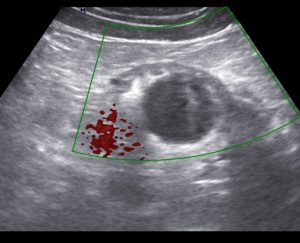

Как выглядит уплотнение в почках на УЗИ

Изменение эхогенности ЧЛС указывает на их уплотнение. Если стенки собирательной системы утолщаются, интенсивность отражения ультразвуковой волны от их поверхности увеличивается. Во время обследования УЗИ-специалист обязательно заметит:

Почка покрыта паренхиматозной тканью, которая обладает невысокой эхогенностью. Но при опухолях или воспалении эхогенность увеличивается в разы.

Заключение УЗИ-специалиста нельзя считать диагнозом. Уплотнение ЧЛС – признак патологических изменений в почке, которые вызываются множеством причин.